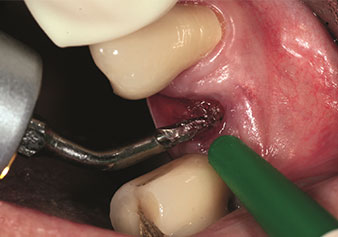

Eine oft unterschätzte Anwendung ist die schonende Extraktion von Zahnwurzeln oder auch von Wurzelfragmenten im Rahmen des Alveolenmanagements. Mit den feinen Periotomen, die aktuell in zwei Ausführungen (EX1 und EX2 von W&H) zur Verfügung stehen, lassen sich auch speziell endodontologisch vorbehandelte Zähne oder ankylosierte Wurzeln mühelos entfernen. Das Ergebnis sind Extraktionsalveolen, deren Hart- und Weichgewebe völlig intakt sind, da in der Regel auf ein Aufklappen verzichtet werden kann.

Dies stellt anschließend eine optimale Basis für eine spätere oder Sofortversorgung mit Implantaten dar (Abbildung eins und zwei mit freundlicher Genehmigung von Dr. Torsten Conrad, Bingen a. Rhein).

Foto: © Dr Torsten Conrad (Bingen a. Rhein)